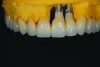

Fig 14. Final ceramics on maxillary arch with implant-retained restoration.

Figure 14